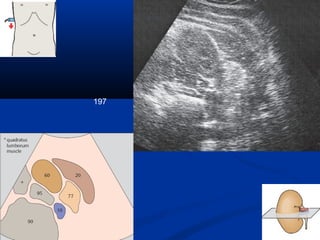

197